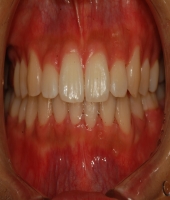

| ● 진료과목 : [심미보철] 돌출치아의 치료

| ● 내용 : 사고로 인한 돌출치아의 치료 |